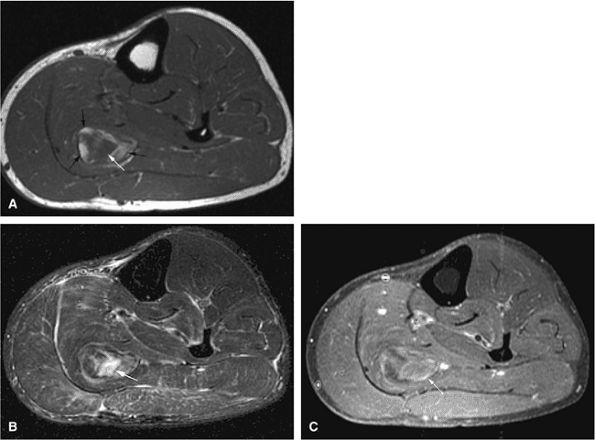

FIGURE 14-9 ● Sagittal (A) and axial (B) T1-weighted images show subcortical osteoid osteoma with a low-signal-intensity nidus (arrow) of the talar neck. (C) Corresponding sagittal fat-suppressed T2-weighted fast spin-echo image demonstrates surrounding hyperintense bone marrow edema (arrowheads). A joint effusion and synovitis is present (arrows). (D) Sagittal CT image demonstrates the osteoid osteoma nidus in the talar neck (arrow).

Intracapsular osteoid osteomas of the hip usually cause a synovial inflammatory response and are associated with joint effusions and variable reactive marrow edema.43,44 Reactive sclerosis demonstrates low signal intensity on T1- and T2-weighted images. There may be extensive marrow edema associated with osteoid osteomas, and STIR or fat-suppressed T2-weighted fast spin-echo sequences can be used to screen for this reactive edema (Fig. 14-9).